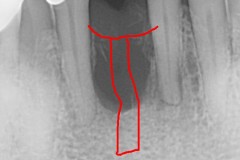

This mouth had recession on just one tooth with very little bone to support the tooth. The area needed support and thickness. The tissue was placed and the area now has thicker tissue to withstand the forces that the patient needs to place on it.

Click on a thumbnail to view the before and after photos.